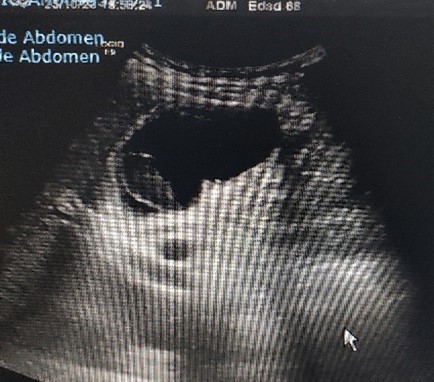

ECOGRAFIA CLÍNICA: Se aprecia vesicular biliar bien repleccionada con imagen en su interior redondeada, hipoecoica, sin sombra, Murphy ecográfico positivo.

Lo llamativo para mi del caso fue visualizar un calculo biliar sin sombra (calculo blando) , saber de su caracteristicas ecograficas y tenerlo como opción diagnóstica.